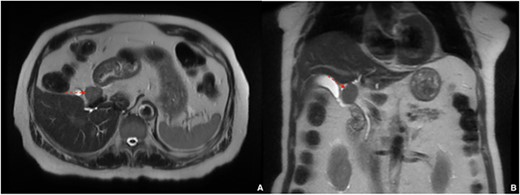

A 77-year-old male with a history of hypertension and hypothyroidism underwent imaging for possible fatty liver disease and was found to have a 3 cm porta hepatis mass causing mild intrahepatic biliary ductal dilation on Magnetic Resonance Elastography (Fig. 1). A multi-phase computed tomography (CT) obtained and showed an isolated 2.8 cm hyperenhancing nodular mass in the liver hilum (Fig. 2). The patient did not have any symptoms, such as jaundice, vomiting, flushing or diarrhea. Physical examination and all biochemical markers were normal, including liver function tests and serum tumor markers (alpha-fetoprotein and carcinoembryonic antigen 19–9). No serologic evidence of hepatitis B or C virus infection was found.

Magnetic resonance elastography showing 3 cm porta hepatis mass causing mild intrahepatic biliary ductal dilation; (A) axial view, (B) coronal view.